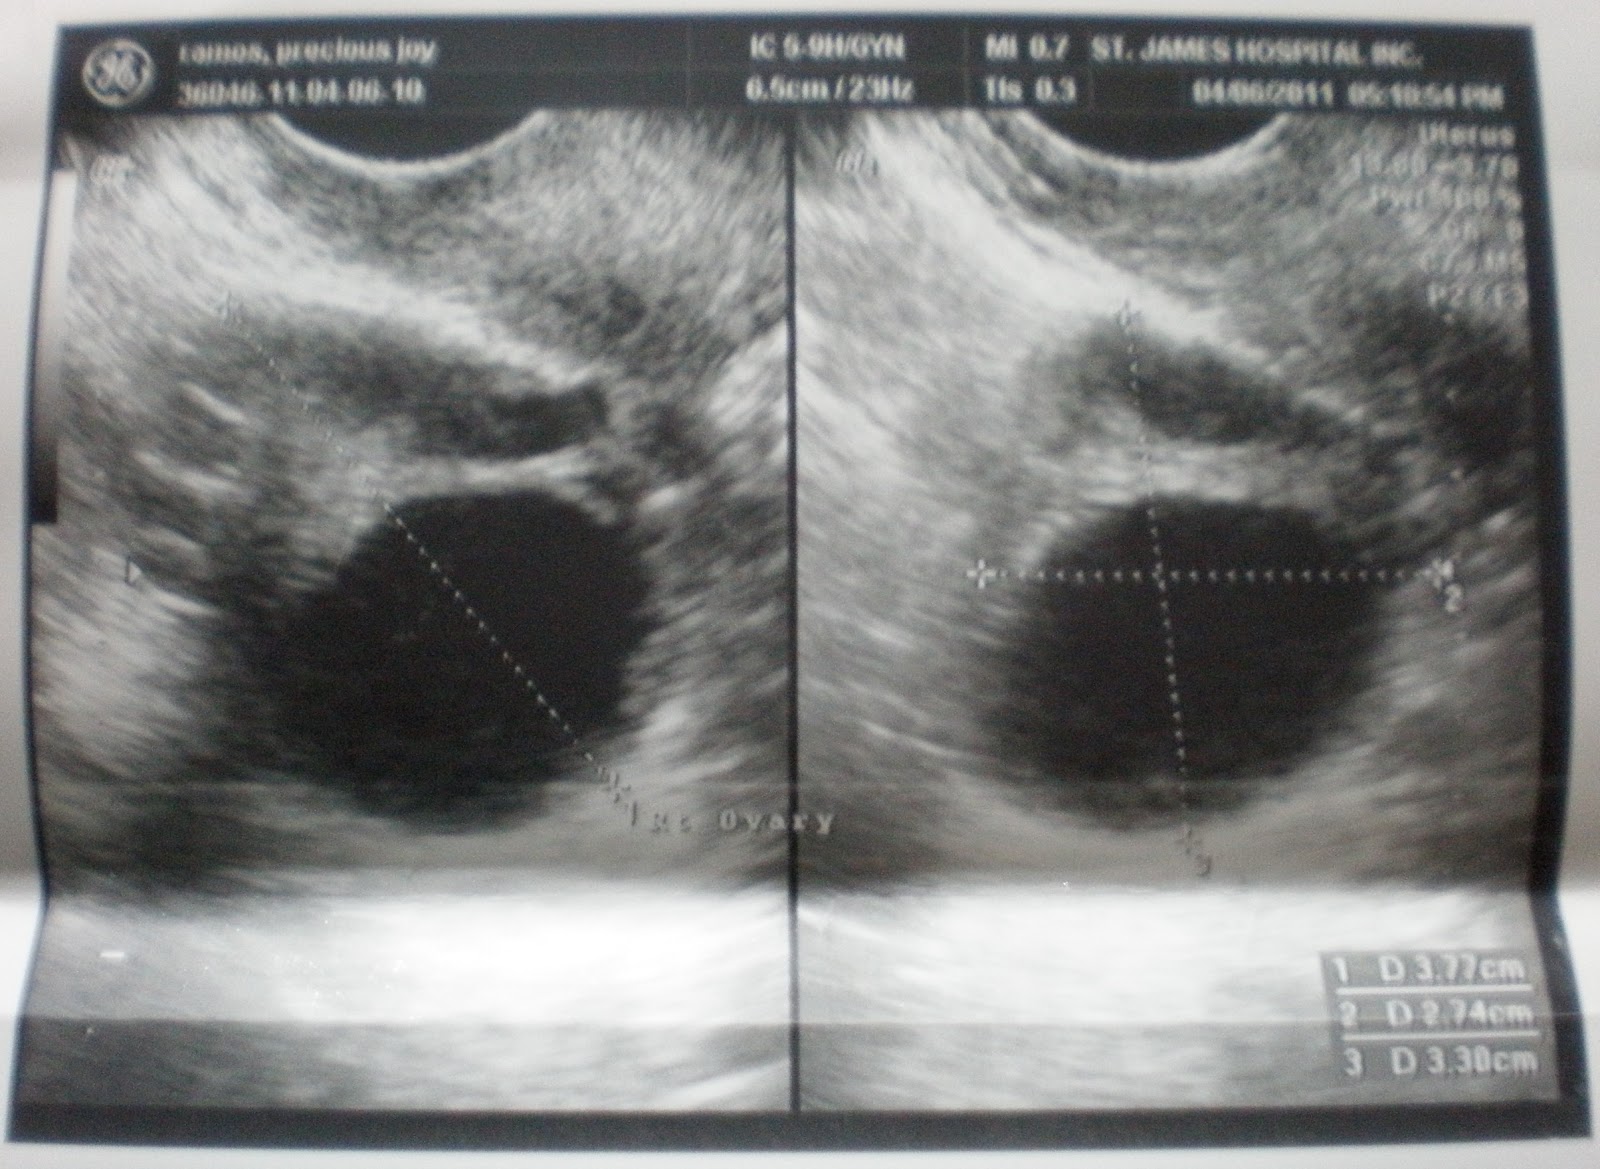

Follicular Study - Folliculometry - The Bong Parenting